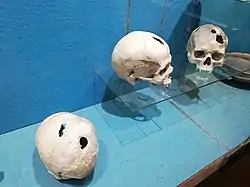

The perimeter of the hole in this trepanated Neolithic skull is rounded off by ingrowth of new bony tissue, indicating that the patient survived the operation.

The perimeter of the hole in this trepanated Neolithic skull is rounded off by ingrowth of new bony tissue, indicating that the patient survived the operation. Skulls from the Bronze Age, exposed at the Musée archéologique de Saint-Raphaël (Archeological Museum of Saint-Raphaël), found in Comps-sur-Artuby (France). The subjects survived operations.

Skulls from the Bronze Age, exposed at the Musée archéologique de Saint-Raphaël (Archeological Museum of Saint-Raphaël), found in Comps-sur-Artuby (France). The subjects survived operations.